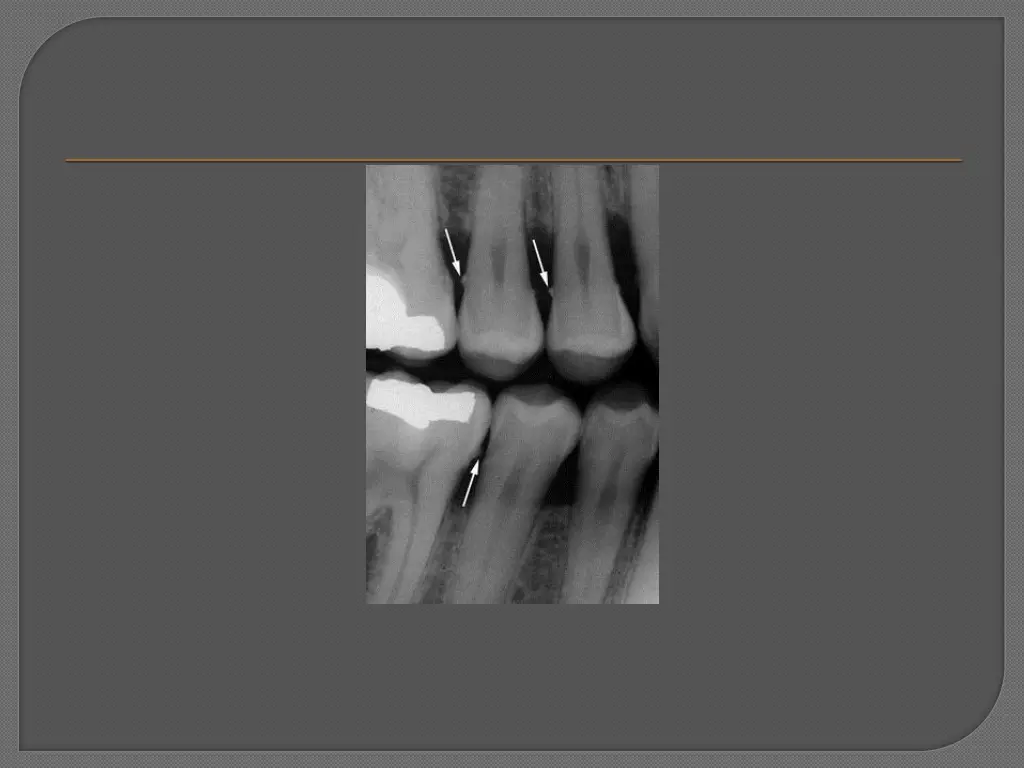

Both supragingival calculus and subgingival calculus may be seen on radiographs . Highly calcified interproximal calculus deposits are readily detectable as radiopaque projections that protrude into the interdental space